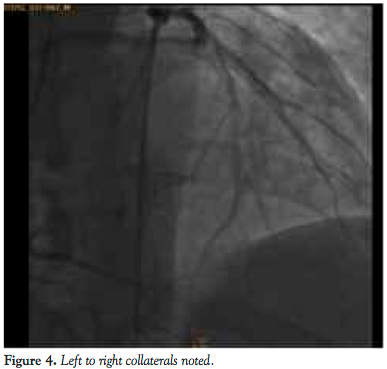

He was admitted for elective cardiac catheterization. Cineangiographic evaluation revealed a single vessel coronary artery arising from the right coronary cusp supplying the entire left system and also the right coronary artery. The right coronary artery was abnormal with significant tortuosity in the proximal and mid segments more consistent with varicose anatomy. Distally the RCA was normal. It gave rise to a posterior descending artery, which had an ostial 60% stenosis. The posterior lateral branch was a small caliber vessel and was normal. The left anterior descending artery (LAD) was a moderate caliber vessel and had no obstructive disease. The first diagonal branch divided into bifurcating branches of which the lower branch had a 70% stenosis. The circumflex artery was a very large caliber vessel that had a proximal 90%-95% stenosis. Left to right collaterals were noted.